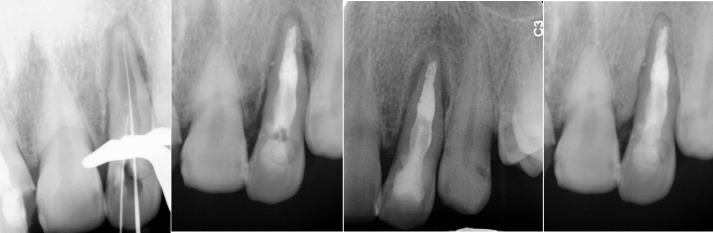

Endodontic treatment in dens invaginatus anomaly is associated with challenges in all stages. This case report outlines the therapy provided for tooth #10 with occasional pain. In examinations, tenderness to percussion and touch and non-response to sensibility tests were observed, and pulp necrosis and symptomatic periapical periodontitis were diagnosed. Radiographic evaluation showed a structural anomaly related to the dens invaginatus and the associated periapical lesion. Cone-beam computed tomography confirmed the presence of DI type II. Endodontic treatment combined with photodynamic therapy and active irrigation using a dental operating microscope was successful and radiographic examinations showed periapical healing along with bone formation in 6-month and 1-year follow-ups.